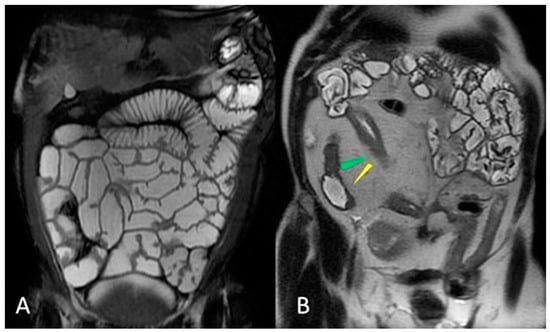

- Guglielmo, F.F.; Anupindi, S.A.; Fletcher, J.G.; Al-Hawary, M.M.; Dillman, J.R.; Grand, D.J.; Bruining, D.H.; Chatterji, M.; Darge, K.; Fidler, J.L.; et al. Small Bowel Crohn Disease at CT and MR Enterography: Imaging Atlas and Glossary of Terms. Radiographics 2020, 40, 354–375. [Google Scholar] [CrossRef]

- Griffin, N.; Grant, L.A.; Anderson, S.; Irving, P.; Sanderson, J. Small bowel MR enterography: Problem solving in Crohn’s disease. Insights Imaging 2012, 3, 251–263. [Google Scholar] [CrossRef] [PubMed]